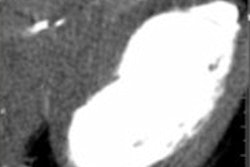

Myocardial perfusion imaging in dual-source CT continues to show promise, and the good news is that using a reconstruction algorithm can remove beam-hardening artifacts. Get the details here.